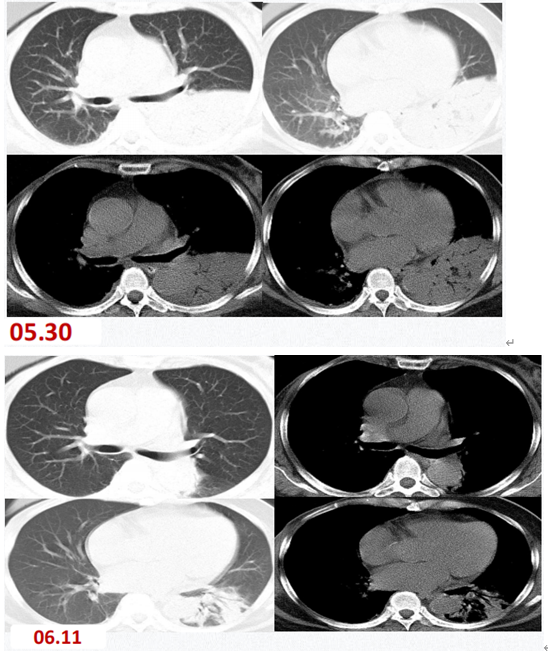

患者,女,52岁,胸闷、气喘2周,加重伴呼吸困难20小时。于2020年3月25日入院,“皮肌炎”病史5个月,规律口服甲泼尼龙、环孢素。胸部CT可见弥漫磨玻璃改变,白肺。第一时间送BALF mNGS,结果回报耶氏肺孢子菌(序列数27115),人类疱疹病毒5型(CMV)(序列数14472),曲霉(序列数3),涂片查到耶氏肺孢子菌,病原学最终诊断:PCP+CMV+曲霉混合感染。给予磺胺+卡泊芬净+更昔洛韦联合治疗,并予以VV-ECMO、IPPV+PPV,最终患者痊愈出院。

图片

治疗前胸部CT

治疗后胸部CT